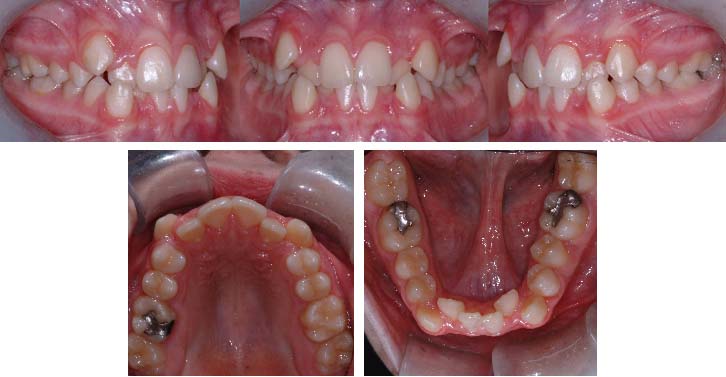

(A) Malocclusion de type classe 2 division 1 avec arcades dentaires étroites et chevauchement sévère dans la région antérieure (femme de 25 ans).

(B) Les vues occlusales permettent d’apprécier le manque d’espace et les rotations dentaires. La gravité du chevauchement ou de l’encombrement dentaire peut nécessiter de l’expansion et/ou des extractions dentaires pour résoudre le manque d’espace.